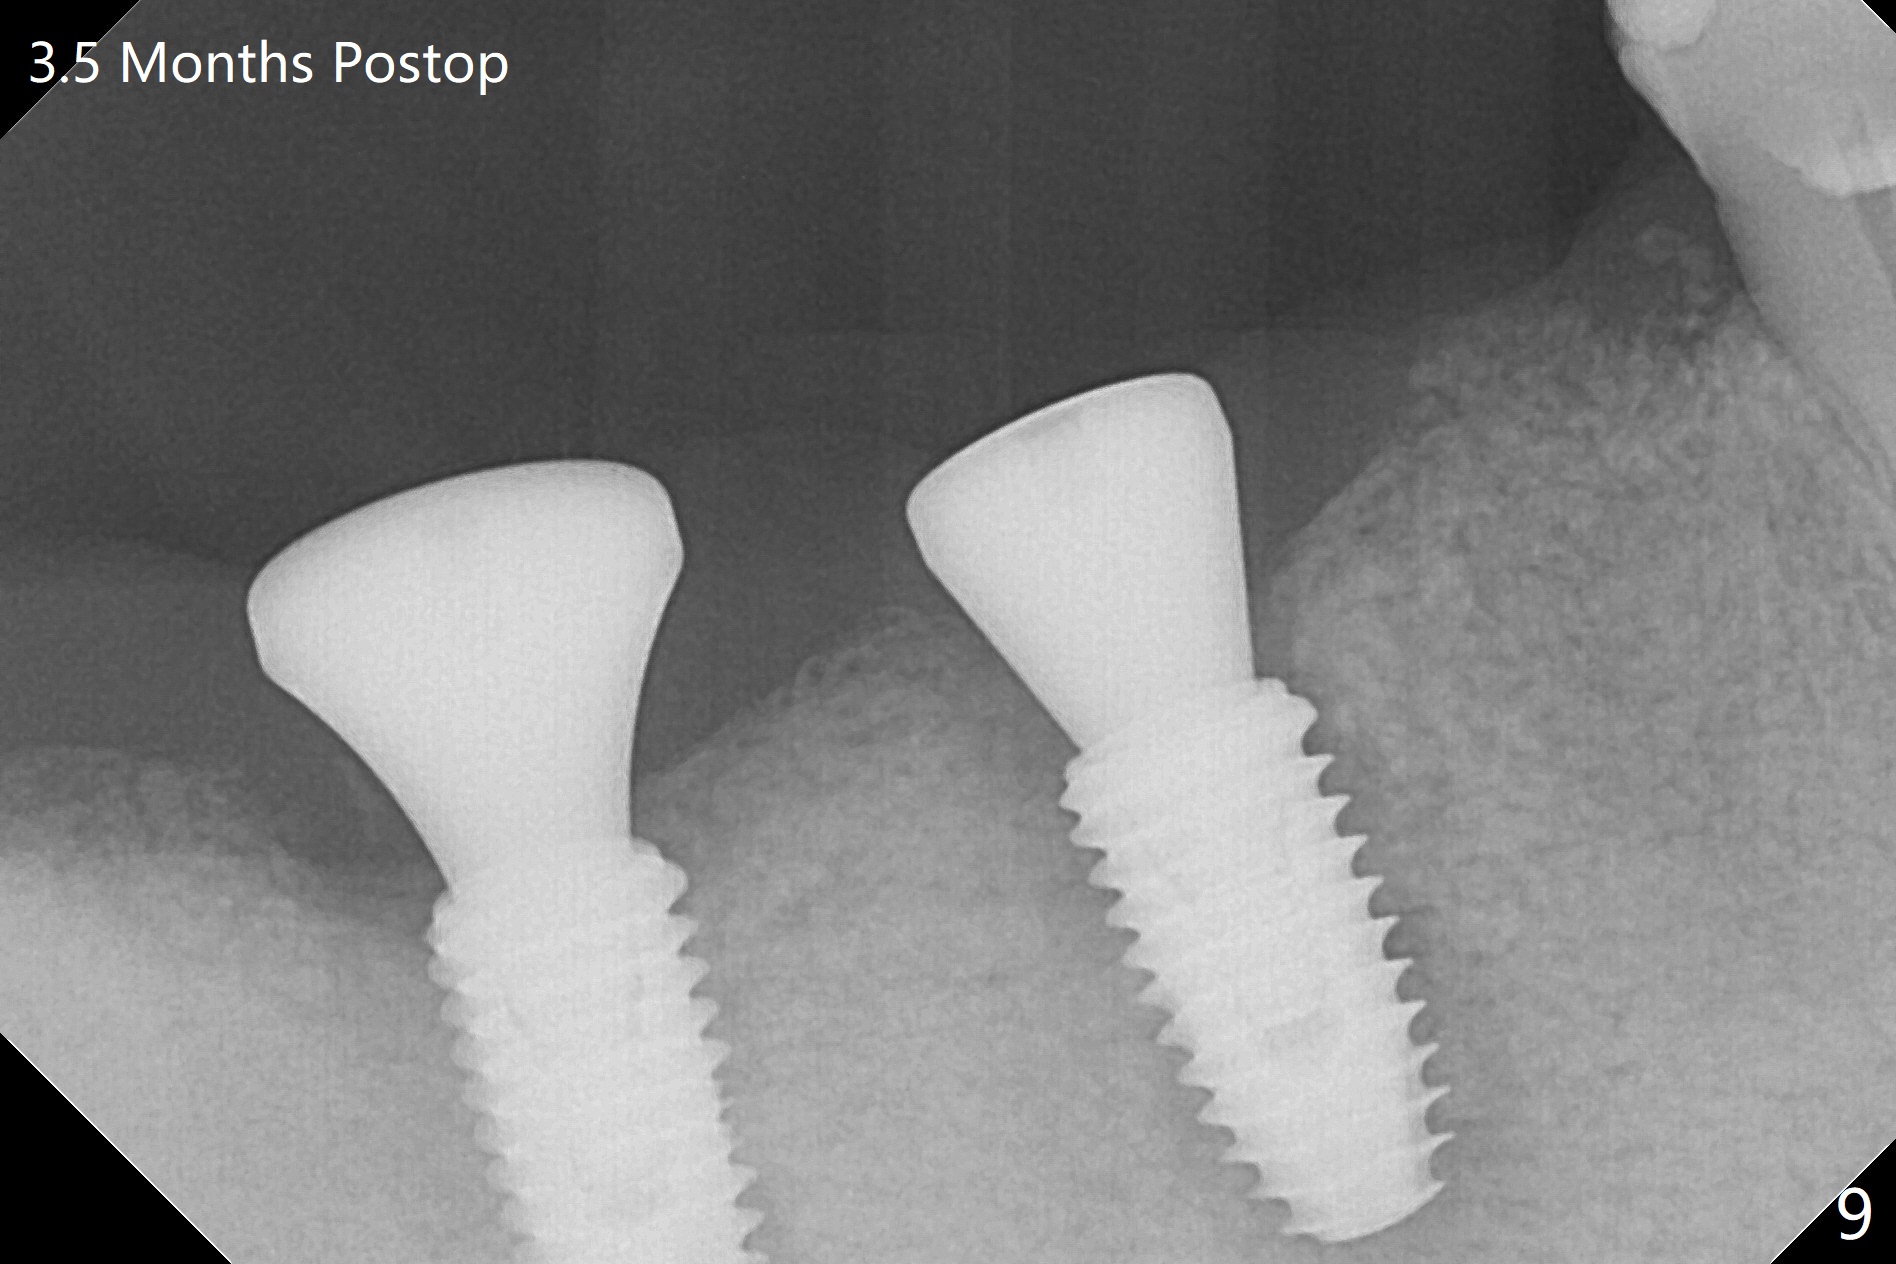

An endodontist refuses RCT retreatment at #29 because of short root. The patient is hesitant about apicoectomy. After discussion of advantages and disadvantages of the latter vs. extraction and implant, the patient chooses the extraction. The latter turns out to be smooth with socket preservation (Fig.4, 5 *). Immediately postop PA shows bone loss at #30 and minor degree around the apex of #31 implant (Fig.4 <), which is probably related with hard bone and bone necrosis due to heat. The headache disappears 1 week postop (Fig.6). The patient does not take pain medication. There is no percussion at #30 (Fig.7). The healing abutments are stable. The patient will return for #30 and 31 restoration nearly 4 months postop and 2 months post #29 extraction. Splinted provisional will be placed if the implants heal. Impression will be taken for #29 guide 4 months post socket preservation. After re-analysis of CT, it appears that a long implant (4x15 mm to gain 3.9 mm fixation in the native bone) will be placed free hand at #29 four months post socket preservation (Fig.8). The bone loss around the implants at #30 and 31 persists 3.5 month postop, while the socket heals at #29 2 months post socket preservation (Fig.9). When the healing abutments with plaque are removed, there is granulation tissue around the gingival cuffs with tenderness. The abutments with heavy plaque (similar to that in Fig.7) are reloaded after cleaning with OHI. The patient returns for CT and impression for #29 guide 3.5 months post socket preservation and 5 months post implant placement. While bone necrosis remains severe at #30, the socket at #29 seems to have healed (Fig.10). Oral hygiene improves with healthy gingiva, but there is tenderness when a cementation abutment is placed. Implant design before and after extraction at #29 (Fig.11,12). Gingiva becomes inflamed at #31 when a splinted provisional is being worn to intrude the opposing supraerupted teeth; bone resorption remains severe in the previous distal socket and the mesial necrotic area (Fig.13 S, N). Pain persists after placement of a healing screw. In spite of severe bone loss, especially distal, the buccal plate is present. When the implant at #31 is removed, there is a large defect with granulation tissue apicobuccal to the buccal plate, corresponding to the presumptive mesial necrotic area (Fig.13,14 N). Vanilla graft mixed with PRF ("sticky bone" too rigid) is placed in the defect, followed by a piece of PRF membrane and 6-month one. The pain appears not to reduce and nearly 1 month later transfers to the buccal of #30.